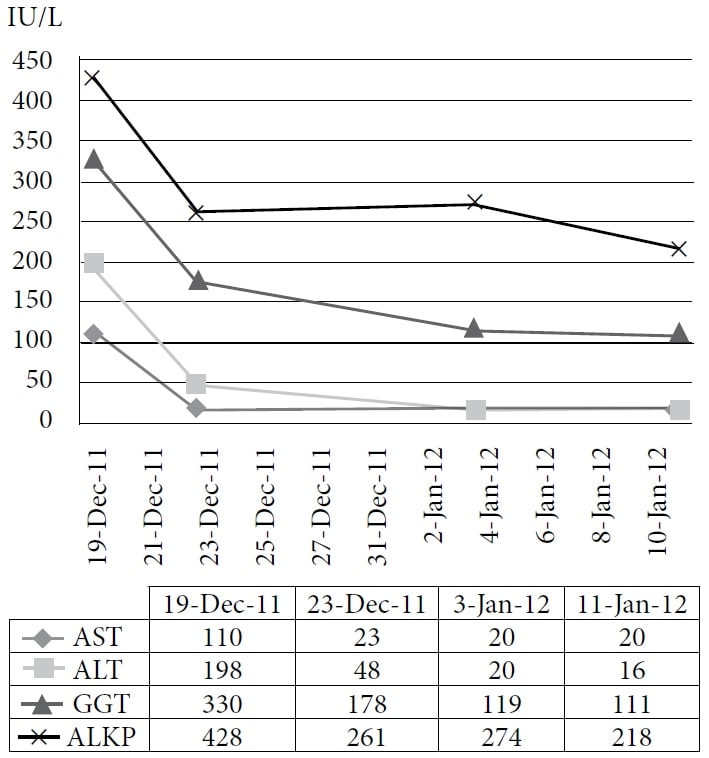

La paziente ha scelto di intraprendere un trattamento naturopatico presso la clinica di un autore, a partire da dicembre 2010. La terapia comprendeva rimedi omeopatici e IVC alla dose di 75 g due volte alla settimana, con un conseguente aumento del livello di energia e del peso. I farmaci e gli integratori in quel momento erano pantoprazolo, alfuzosina, metoprololo, ramipril, simvastatina, amlodipina, clopidogrel, vitamina D, complesso vitaminico B, acidophilus e acido α-lipoico. Il paziente ha continuato il trattamento fino al 2011 con un buon controllo dei sintomi; tuttavia, il suo CEA ha continuato ad aumentare. Una TAC effettuata nel novembre 2011 ha dimostrato una malattia epatica metastatica estesa e diffusa e numerosi noduli polmonari in espansione, coerenti con una progressione della malattia a intervalli. Il paziente ha quindi scelto di intraprendere un ciclo di prova di DCA per via endovenosa. Il 19 dicembre 2011 sono stati eseguiti gli esami del sangue di base, tra cui il CEA e gli enzimi epatici. La prima dose di 3000 mg (41 mg/kg) di DCA per via endovenosa è stata somministrata il 22 dicembre 2011, insieme a 50 g di IVC. Un test CEA era stato programmato per essere eseguito 4 settimane dopo, ma è stato erroneamente ripetuto 1 giorno dopo l’infusione, insieme alla misurazione degli enzimi epatici. È stata notata una rapida riduzione degli enzimi epatici e del CEA. (Vedi Figura 1 e Figura 2)

Abbreviazioni: AST = aspartato aminotransferasi; ALT = alanina aminotransferasi; GGT = γ-glutamil transpeptidasi; ALKP = fosfatasi alcalina.

La figura mostra l’immediato brusco calo e la continua diminuzione degli enzimi epatici con la somministrazione di DCA per via endovenosa.

La seconda infusione di DCA è stata somministrata 6 giorni dopo alla dose di 3500 mg (48 mg/kg) insieme a 35 g di IVC. Dopo l’infusione, il paziente ha notato nuovi sintomi: brividi, sudorazione e affaticamento. Una terza infusione di DCA alla dose di 3700 mg (50 mg/kg) e 50 g di IVC è stata somministrata 8 giorni dopo la seconda dose, con successivi esami del sangue che hanno mostrato ulteriori miglioramenti (Figura 2).

Il caso 1 illustra la risposta biochimica di un carcinoma metastatico del colon alla terapia DCA per via endovenosa, combinata con IVC ad alte dosi. In precedenza, il CEA del paziente era aumentato costantemente mentre utilizzava solo l’IVC per 10 mesi. Pertanto, la diminuzione del CEA può essere attribuita alla terapia con DCA. Poiché la letteratura riporta una potenziale riduzione del CEA di oltre il 50% entro 10 ore dalla metastatectomia epatica,40 un’ampia diminuzione del CEA a 1 giorno da qualsiasi altra terapia è plausibile se il tumore ha risposto rapidamente e non deve essere considerato un risultato errato. Inoltre, il rapido calo degli enzimi epatici è coerente con una riduzione del danno epatico derivante dalla morte delle cellule tumorali o dall’inibizione della crescita.